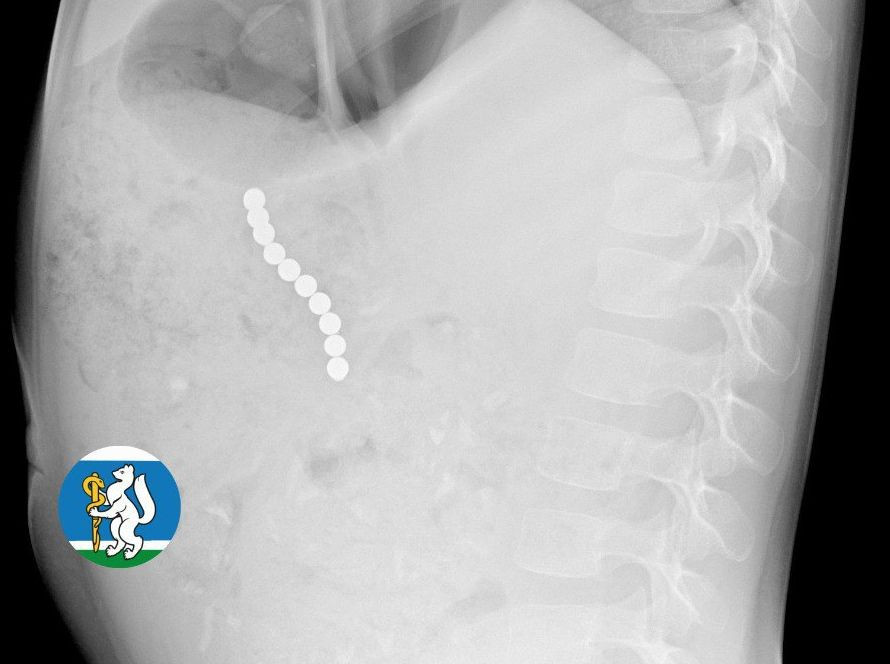

Ребёнок почувствовал себя плохо. На рентгене врачи увидели цепочку магнитных шариков, которые травмировали пищеварительную систему, из-за чего мог развиться перитонит. Девочку экстренно доставили в больницу.

При операции хирурги достали 10 магнитных шаров, общей длиной 5 см. Девочка 10 дней провела в больнице, а после этого её выписали домой. Сейчас её жизнь вне опасности.